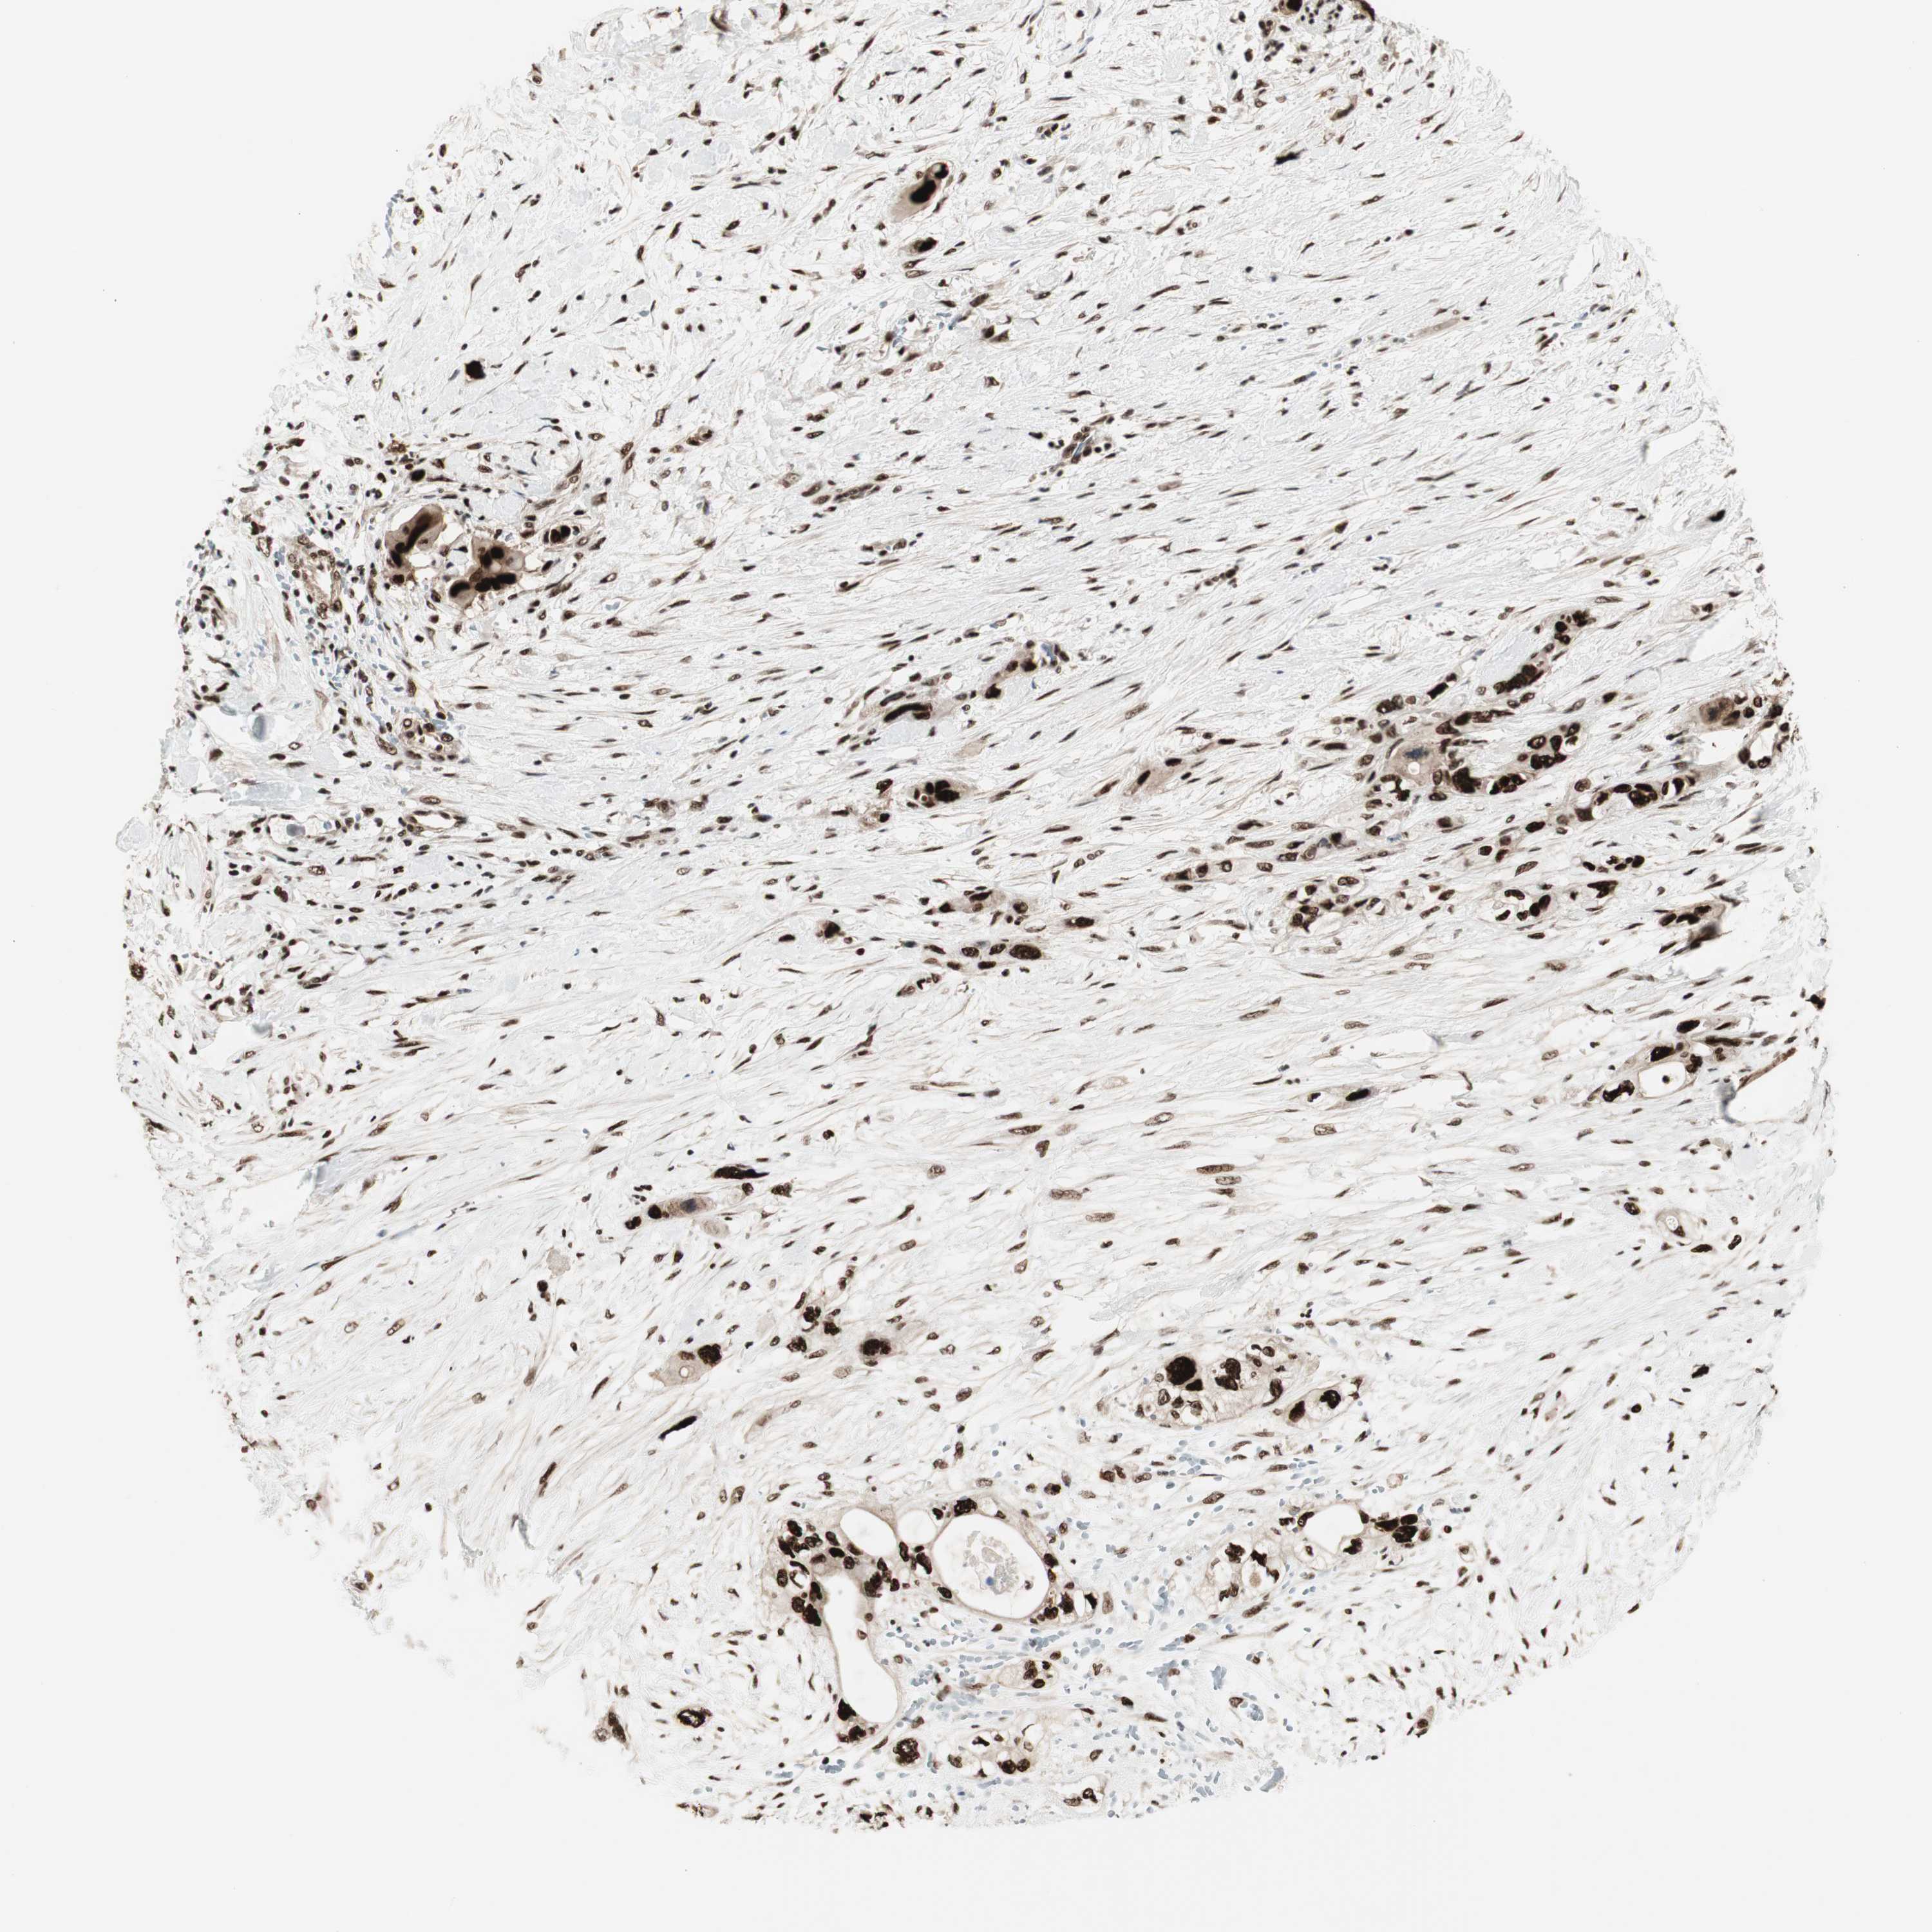

PANCREATIC CANCER - Protein expressioni

A mouse-over function shows sample information and annotation data. Click on an image to view it in a full screen mode. Samples can be filtered based on level of antibody staining by selecting one or several of the following categories: high, medium, low and not detected. The assay and annotation is described here.

Note that samples used for immunohistochemistry by the Human Protein Atlas do not correspond to samples in the TCGA dataset.

Antibody stainingi

Antibody staining in the annotated cell types in the current human tissue is reported as not detected, low, medium, or high, based on conventional immunohistochemistry profiling in selected tissues. This score is based on the combination of the staining intensity and fraction of stained cells.

Each image is clickable and will lead to virtual microscopy that enables deeper exploration of all samples and also displays staining intensity scores, fraction scores and subcellular localization as well as patient and tissue information for each sample.

Antibody HPA008926

Antibody CAB011625

Staining

High

Medium

Low

Not detected

Intensity

Strong

Moderate

Weak

Negative

Quantity

>75%

75%-25%

<25%

None

Location

Nuclear

Cytoplasmic/membranous

Cytoplasmic/membranous,nuclear

Adenocarcinoma, NOS

Adenocarcinoma, metastatic, NOS